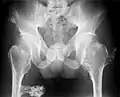

Multiple osteochondromas causing deformity of the forearm (shortening of the Radius with secondary bowing of the Ulna).

multiple osteochondromas at the pelvis